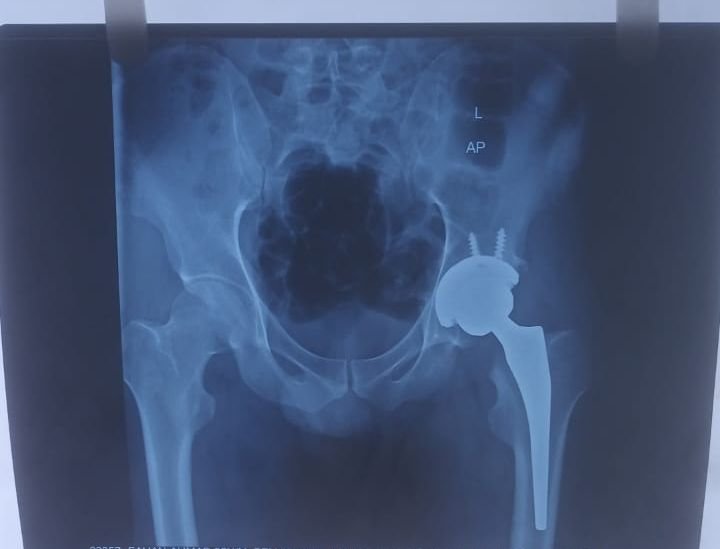

Hip Replacement